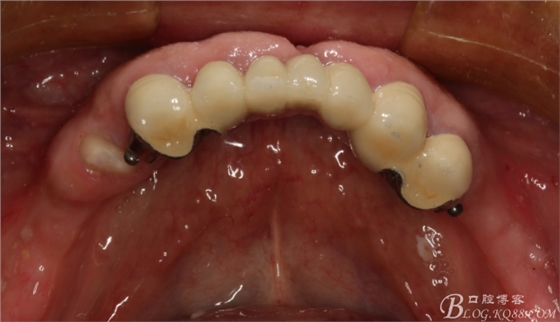

上頜基牙比較分散,選擇 5顆基牙的套筒冠修復(fù),

鈷鉻合金金屬內(nèi)冠

套筒冠外冠

修復(fù)后效果圖,